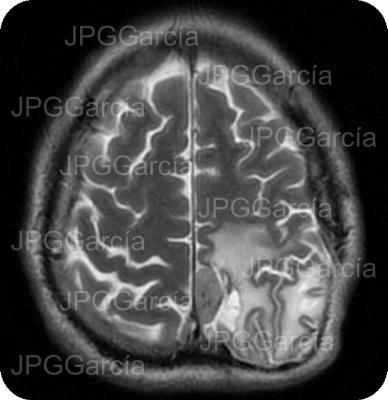

Tumor del plano esfenoidal clasificado por imagen como Meningioma visto a través de resonancia magnética cortes axial y coronal